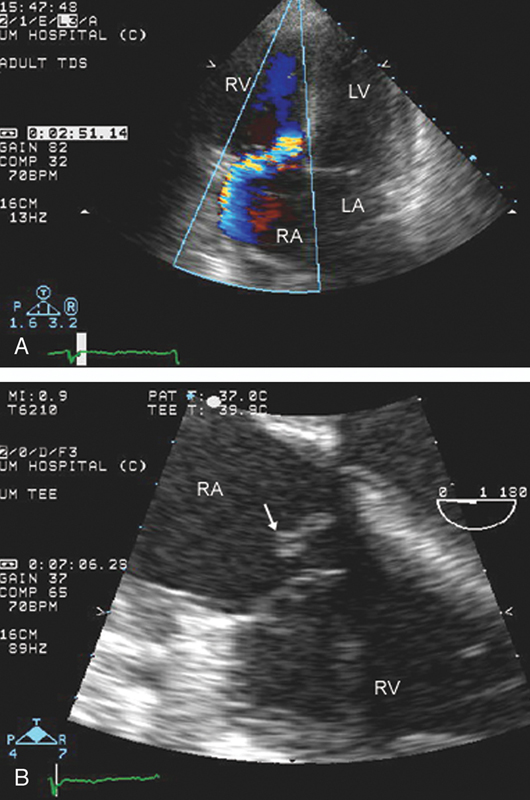

فحوصات تشخيصية لبعض امراض القلب والشرايين التاجية